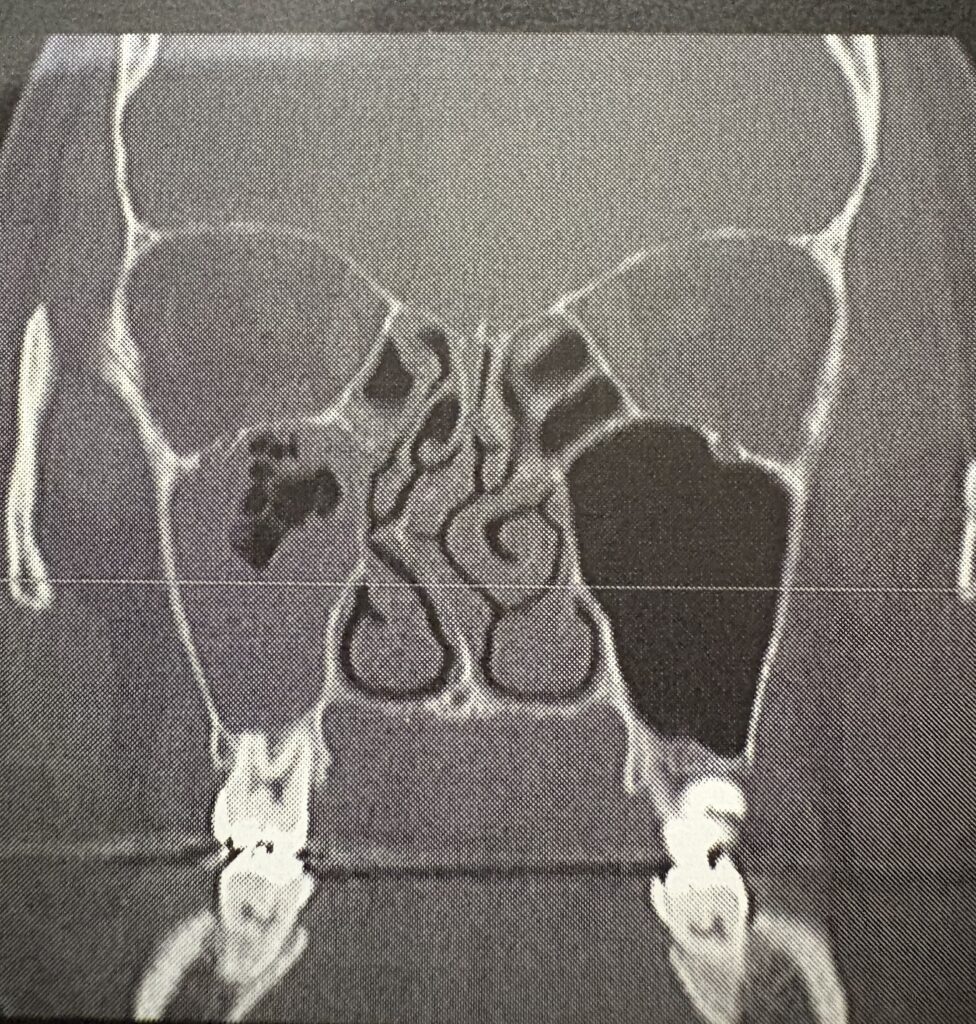

診察では、以前撮ったCT画像を見ながら

・鼻中隔の曲がりが強い

・空いたスペースに鼻甲介が肥大している

・まっすぐにするのは難しい

と言われつつも、

👉 「なんとかするよ」

とのこと。

↓実際の私の鼻のCT画像